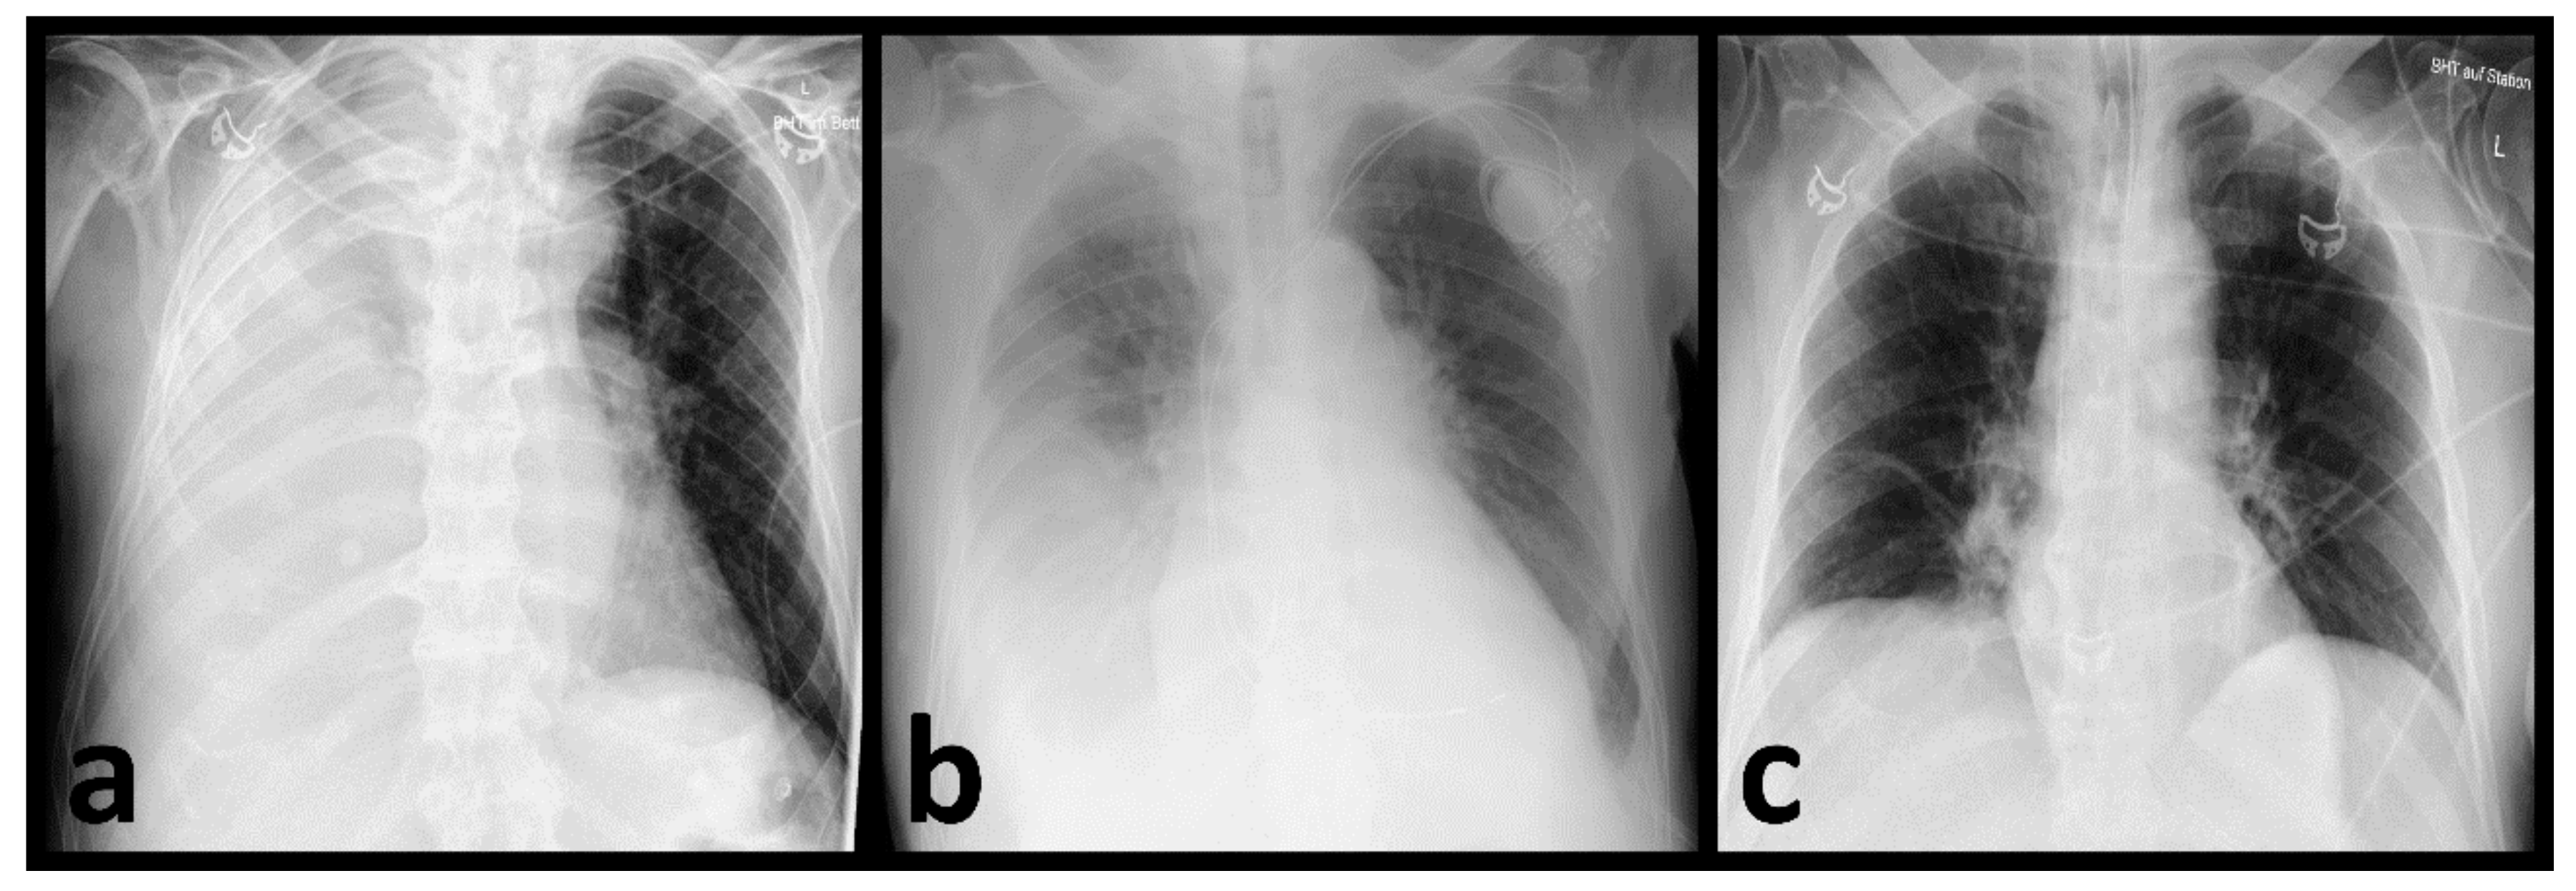

2.2. Imaging Evaluation

3.2. Identification of Pneumonia by Radiologists

3.3. AI-Based Diagnostic Performance